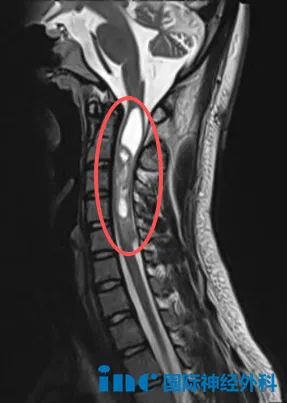

6歲女孩樂樂,在1個多月前被查出小腦占位,一度令樂樂一家陷入前所未有的迷茫和無助中。核磁上巨大的腫瘤,讓原本活潑開朗的女兒變得頭暈頭痛、嗜睡……而導致這一切的罪魁禍首卻一直得不到解決,這對樂樂父母來說,每一天都是煎熬。

影像